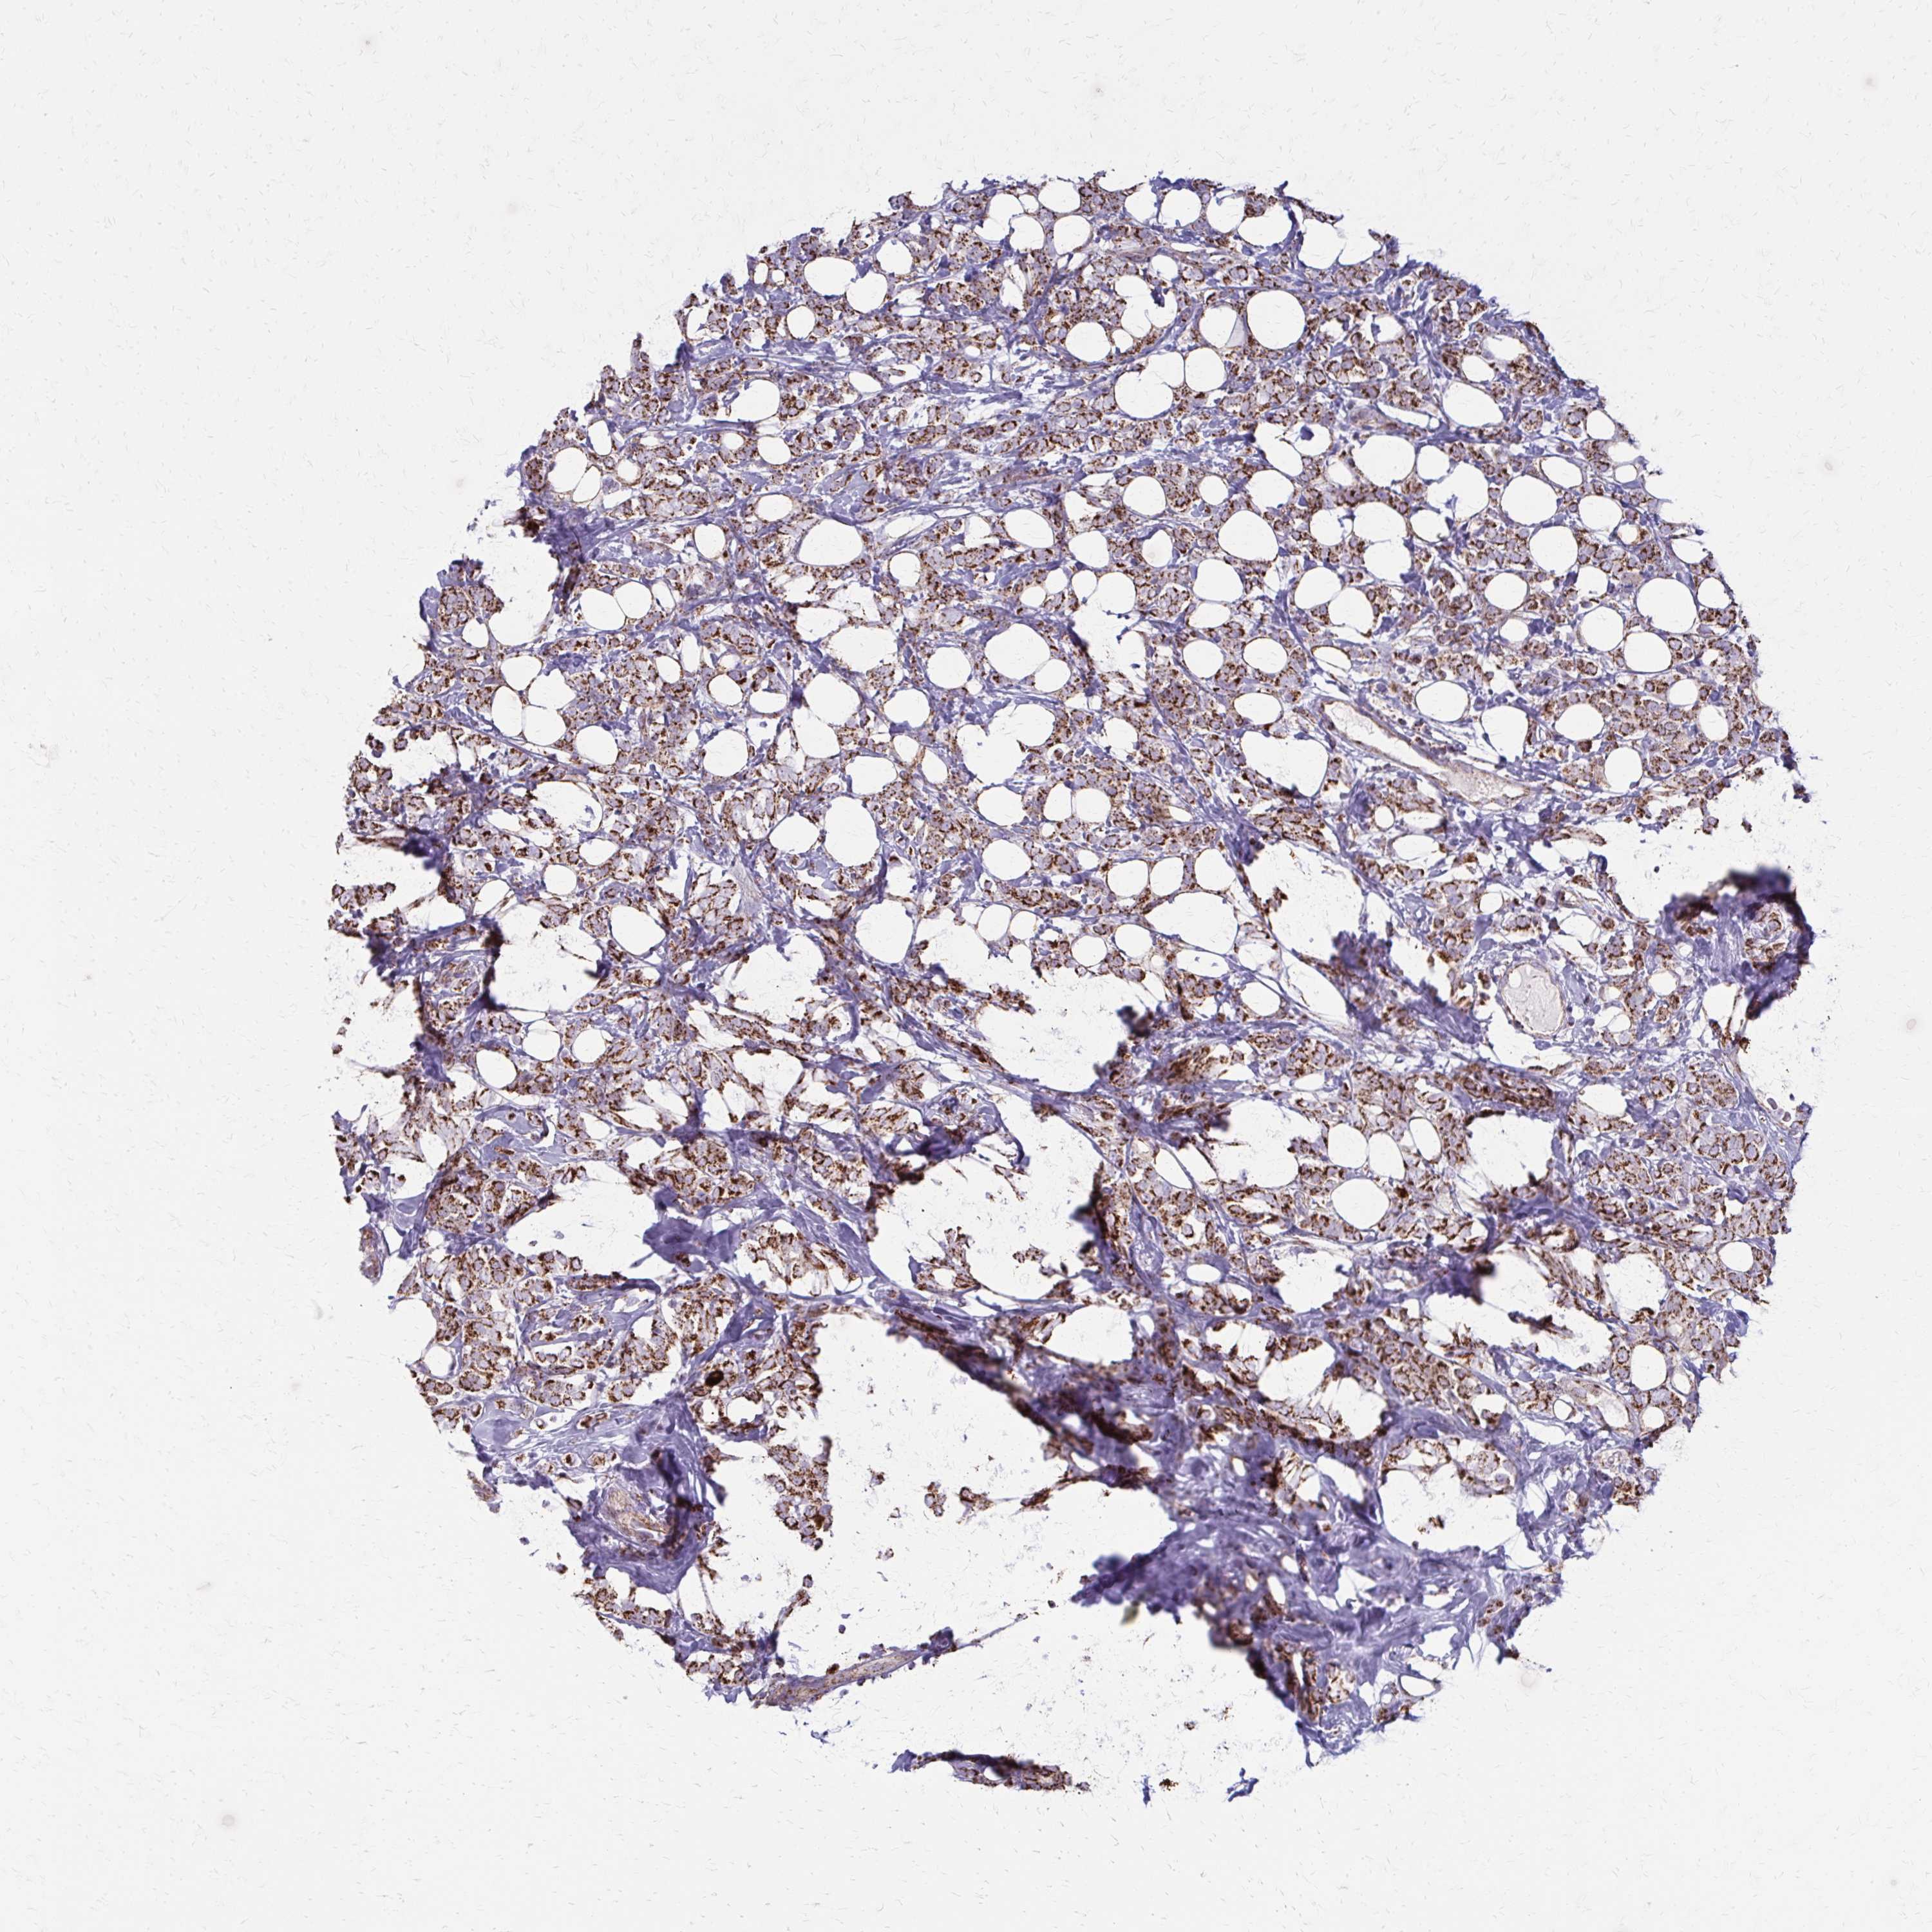

CANCER BREAST CANCER Show tissue menu

BRCA TCGA BRCA VALIDATION PROTEIN EXPRESSION